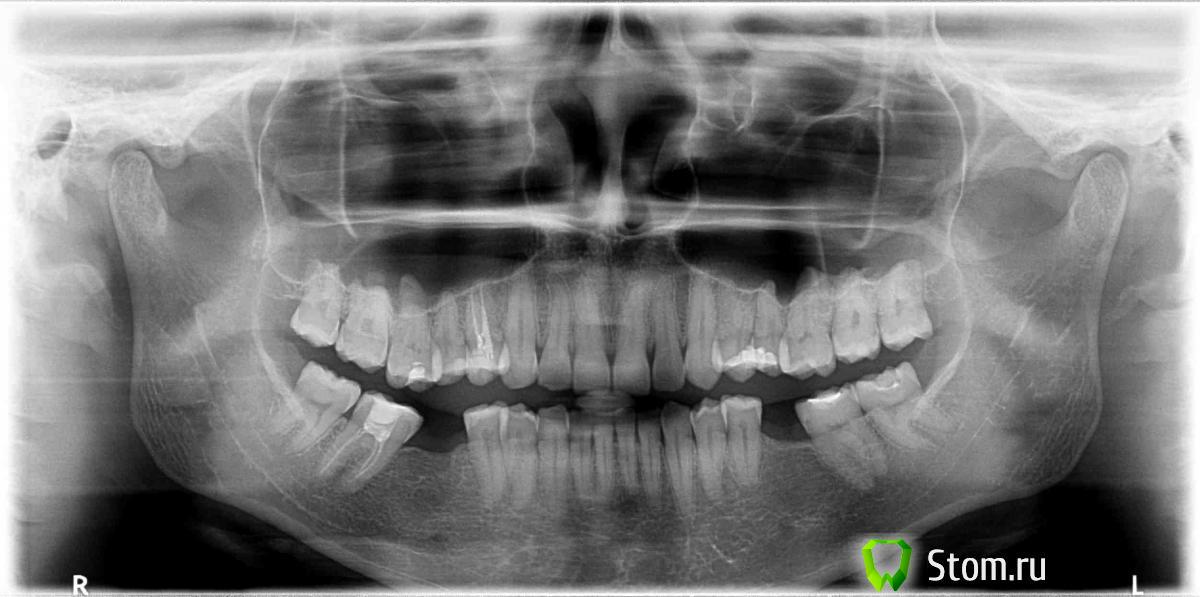

FBR Опубликовано 22 марта, 2012 Поделиться Опубликовано 22 марта, 2012 (изменено) Спасибо! Буду соблюдать! А снимок нормальный? Там правда ничего нет? Просто врач сказал что ничего не видит.. но болит же жутко!"ампулу ибупрофена"сообщите о результате терапии если не затруднито снимке: необходимо протезировать отсутствующие зубы. т.к. меняется линия смыкания зубов. И смущают суставные головки ВНЧС справа слева. Изменено 22 марта, 2012 пользователем FBR Ссылка на комментарий

LinneLee Опубликовано 22 марта, 2012 Автор Поделиться Опубликовано 22 марта, 2012 "ампулу ибупрофена"сообщите о результате терапии если не затруднито снимке: необходимо протезировать отсутствующие зубы. т.к. меняется линия смыкания зубов. И смущают суставные головки ВНЧС справа слева. В каком смысле смущают? У меня как раз справа всё и болит... П.С. А это не похоже на опухоль какую-нибудь? А то ведь лимфоузлы еще, правда они маленькие, на днях пойду УЗИ сделаю... накрутила себе уже всякого от отчаяния... Ссылка на комментарий